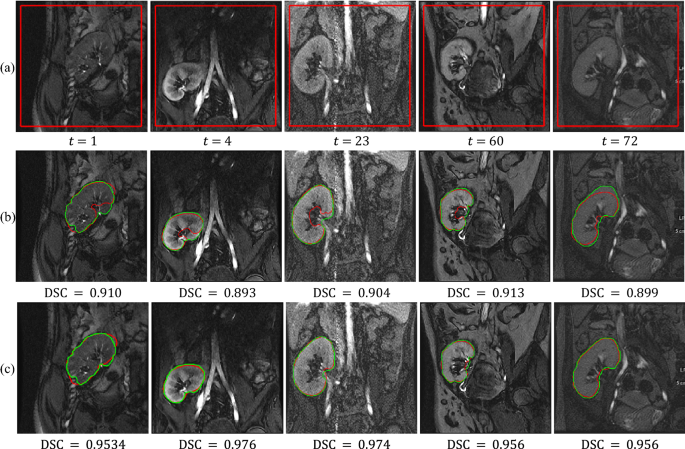

As reported in Table 1, the FML method achieves better segmentation results than the FCMLS method by providing higher mean DSC values and lower standard deviations. Moreover, the lower mean and standard deviation of HD95 values of the proposed method confirm its notable better segmentation performance than FCMLS. The standard deviation of HD95 of the FML method is significantly lower than FCMLS method which confirms that the FML method is more consistent and stable than the previous method. We can observe the significant difference between the segmentation performances of the two methods with low-contrast images. This indeed confirms that the superiority of the new FML method. Figure 3 visually shows the performance of the FML and FCMLS methods on 5 varying-contrast images of different subjects.

Segmentation results of FML vs. FCMLS. (a) DCE-MRI kidney images with initial LS contour. Segmentation results outlined in red with DSC values for the kidneys segmented by FCMLS in (b) and FML in (c). The ground-truth segmentations are superimposed on the images in green. Please refer to Supplementary Fig. S3 online for better visualization of segmentation results.

It can be observed from Fig. 3 that the segmentation accuracy has been notably enhanced using the FML method compared to FCMLS method. The original images are shown in the first row with an initial LS contour. The second and third rows show segmentation results of the FCMLS and FML methods, associated with the DSC values with respect to the ground-truth. The results also show that the FML method can output notably accurate segmentation results on low-contrast images compared against FCMLS method. From the time performance perspective, our comparative experiments demonstrate the faster convergence rate of the new FML method as it completes the evolution process after about 30 iterations, whereas the previous FCMLS method takes more than 40 iterations to converge. Furthermore, we compare the obtained results with the results obtained from other well-known segmentation methods, namely, the 2nd-order MGRF level-set (2nd-MGRF)5, shape-based (SB)31, vector level-set (VLS)32, and parametric kernel graph cut (PKGC)33, see Table 2.